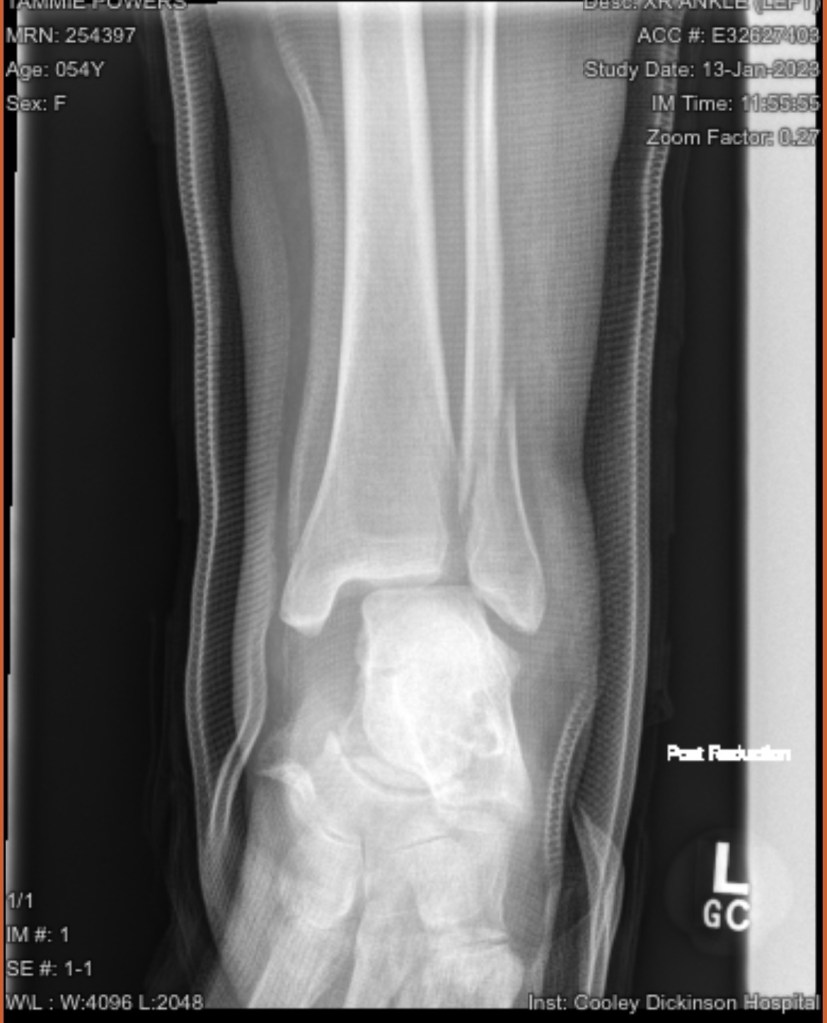

Once I got there they stuck me in a room, and finally did some x-rays. After some prodding they gave me some pain meds, and a diagnosis. A bimalleolar fracture with ligament and tendon damage.

Then came the fun part, a shot of lidocaine in the joint, and 2 doctors reducing the fracture to get it close to the way it was. I went home with pain meds , crutches and instructions to go to Cooley ortho walk in on Monday.

Walk in ortho clinic gave me the results that I expected, but didn’t want. It would be a surgical repair. On January 23, I was at the Kittredge Surgical Center at 6:00 am. My ankle was pinned, plated, the talus was relocated and the ligaments and tendons were repaired. It is likely that the incision went right through my tattoo. So eventually that will need to be repaired as well. I will be non weight bearing for 8-12 weeks, my knee scooter has become my best friend. Because crutches and I don’t get along.